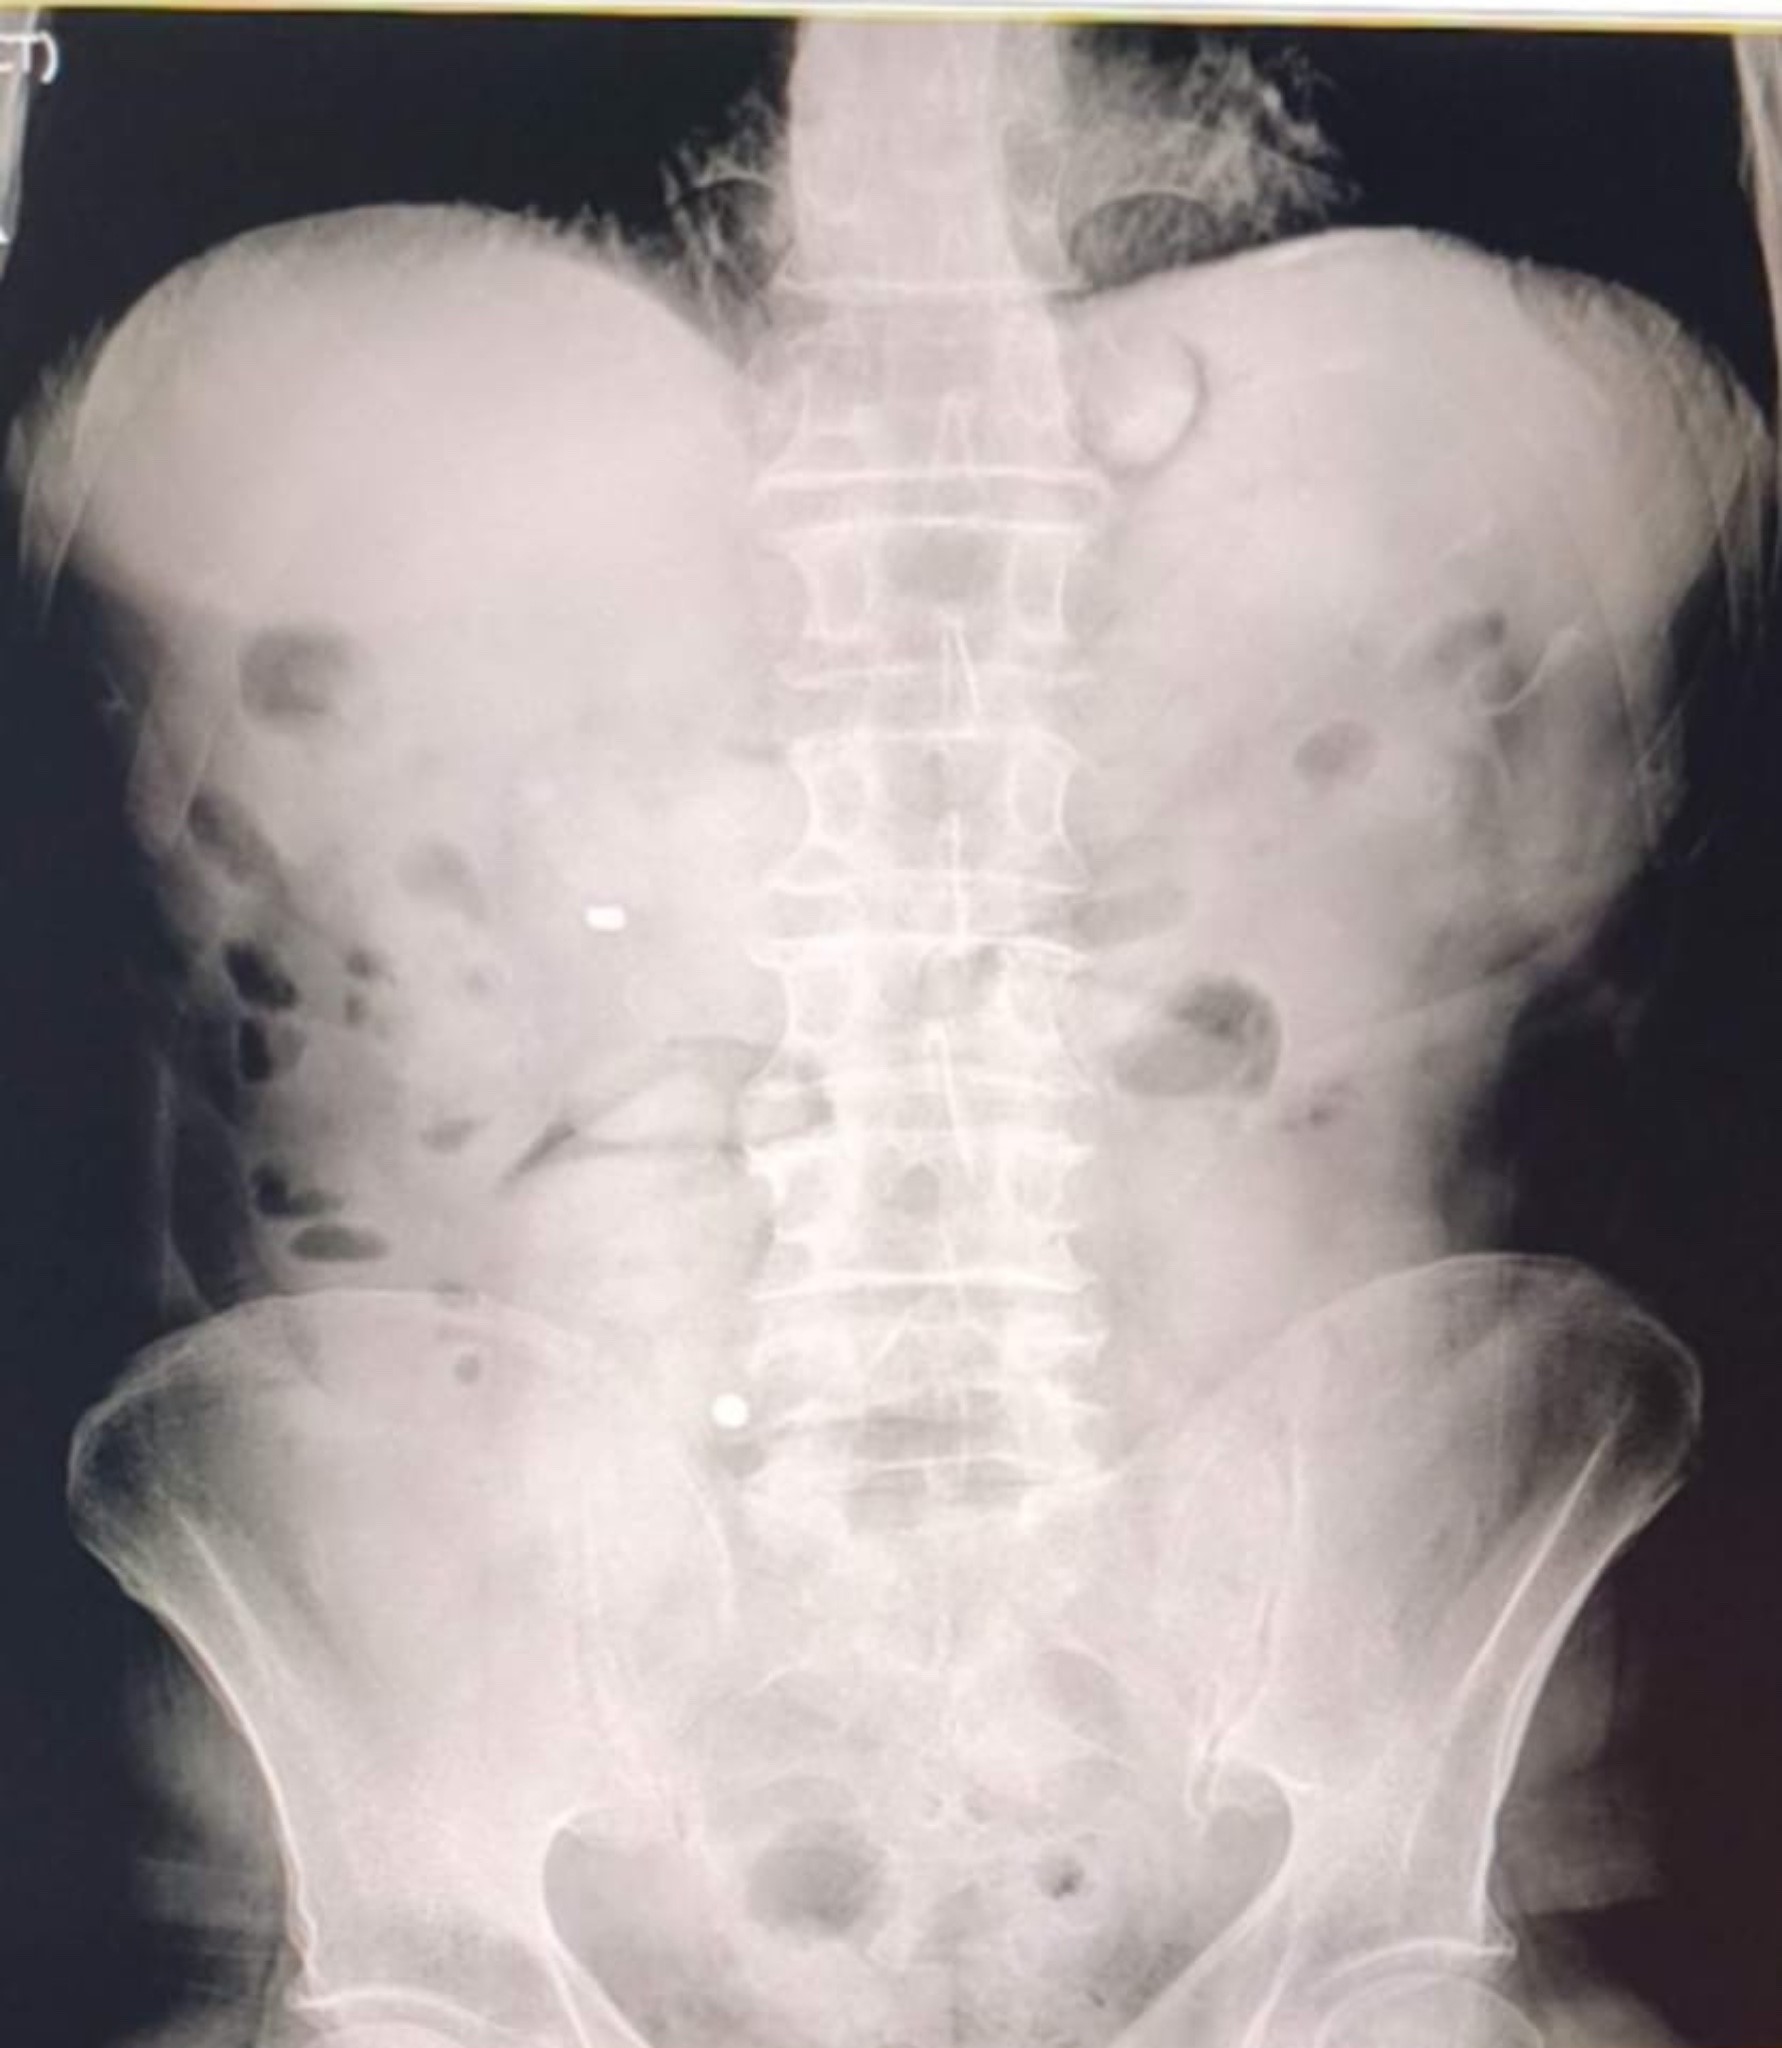

Taksinin yolcu koltuğunda bulunan İran uyruklu D.G. ve A.C. gözaltına alındı. Şüphelilerin hastanede yapılan kontrolleri ve çekilen röntgen görüntülerinde mide ve bağırsaklarında çok sayıda kapsül olduğu belirlendi.

Doktor gözetiminde yapılan müdahale sonucu toplam 93 kapsül halinde 1 kilo 70 gram metamfetamin ele geçirildi.